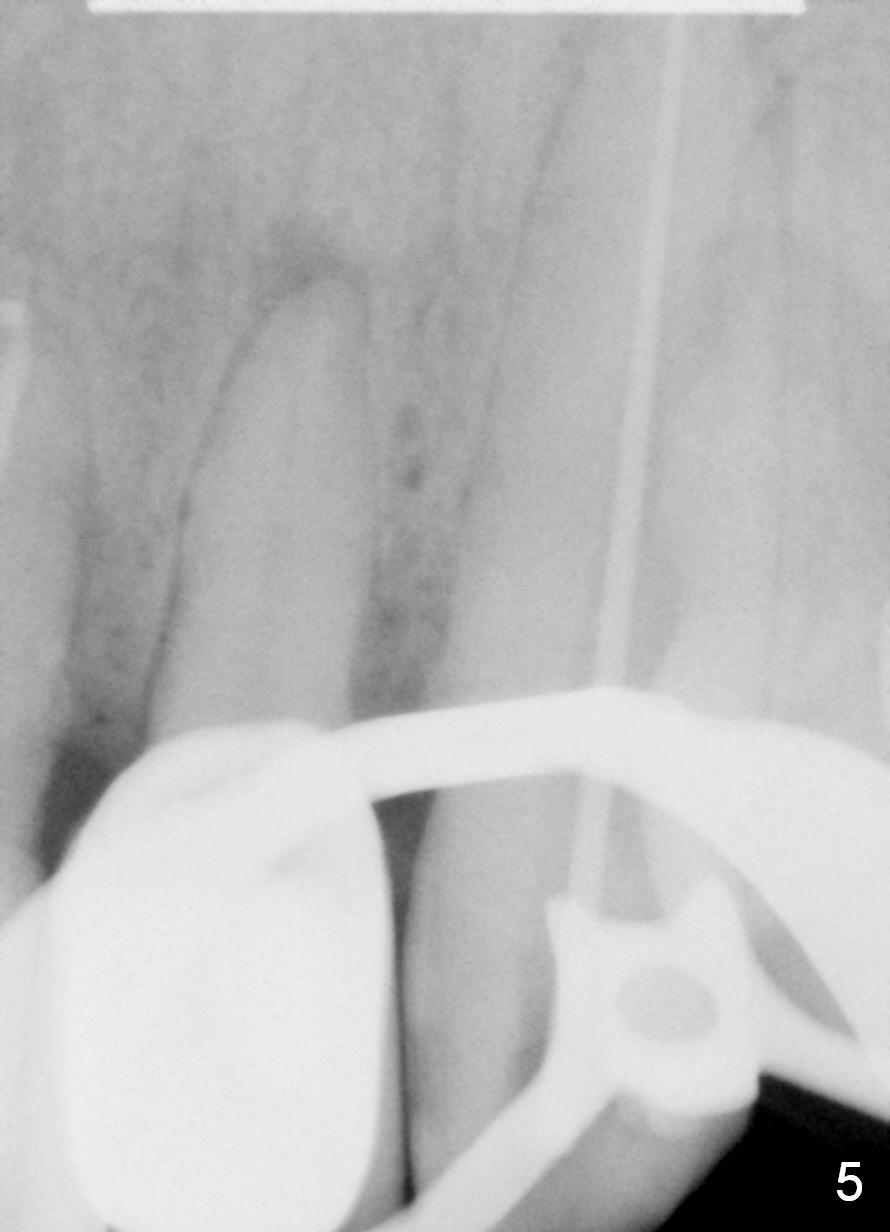

A 57-year-old man has multiple restoration. There was a fistula mesiobuccal to #11 a year ago (Fig.1,2). There is acute apical infection lately. The pulp is non-vital. Apex locator is sensitive. Two PAs are taken with #15 file at 29 mm and 33 mm (Fig.3,4). The canal is debrided until #40 hand file. The master cone with length of 28 mm is inserted below the landmark (Fig.5). Panoramic X-ray is taken for final confirmation (Fig.6).